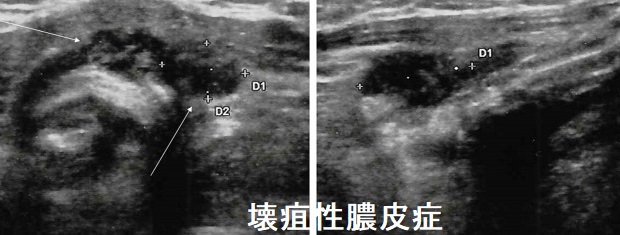

壊疽性膿皮症は自己免疫性皮膚炎で、好中球性の皮膚壊死が特徴。腹部~下肢に好発し、わずかな外傷が数週間の間に、毛包炎→膿疱→辺縁が隆起する穿掘性潰瘍へ急速進展します。自己免疫性なので細菌培養は陰性。

甲状腺腺腫様結節が基礎疾患だった壊疽性膿皮

甲状腺腺腫様結節が基礎疾患だった壊疽性膿皮症が報告されています(Ann Dermatol Venereol. 1987;114(10):1229-34.)